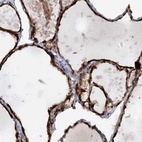

Immunohistochemical staining of human thyroid gland shows strong cytoplasmic positivity in glandular cells.